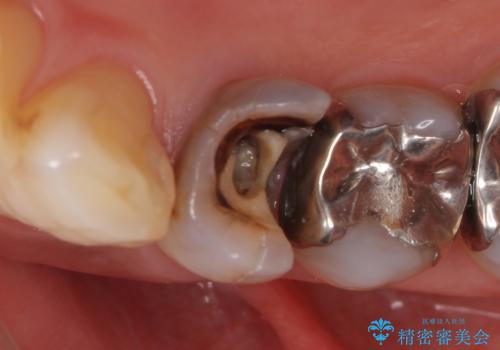

- 他院にて左下4の根管治療を行っていたが、疼くような痛みが引かないため当院にいらっしゃった方の症例です。

左下4の再根管治療を行い症状が治まったのち、オールセラミッククラウンによる補綴を行いました。